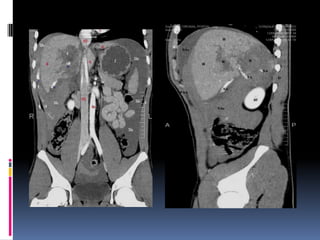

INJURIA PANCREÁTICA  Resultade la compresión de la glándula contra la columna vertebral  Manubrio de bicicleta  Clínica y laboratorio inicialmente inespecíficos

 Signos indirectosde lesión traumática  Agrandamiento difuso  Grasa peripancreática “sucia”  Líquido periglandular  Engrosamiento fascia pararrenal anterior